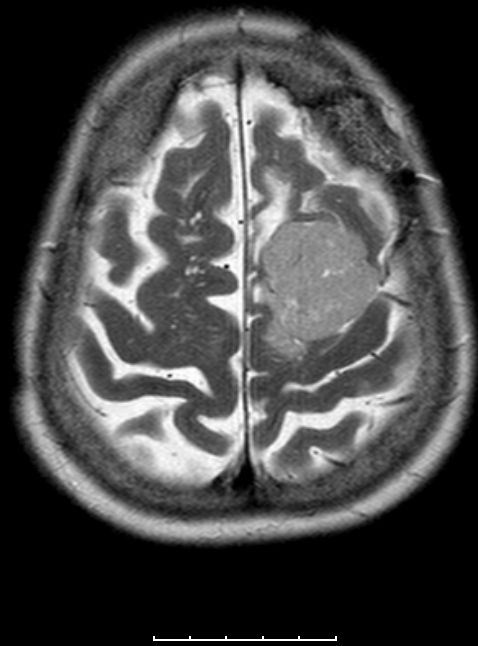

| zurück Home | Meningeom parietal | |||

72-jährige Patientin mit Teilparese des rechten Beins, passageren Sprachstörungen und Krampfanfall vor 6 Monaten. | |||

Postoperative Histologie: Meningeom Grad 1 | . | ||

Rezidiv 2 Jahre später. Postoperative Histologie: atypisches Meningeom II°![]() |